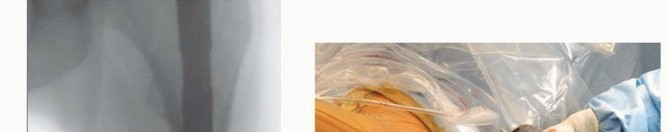

Fracture Reduction and Canal Preparation

A fracture reducer (TriGen) or similar curved cannulated device is inserted through the retained channel reamer to the fracture site and threaded through the fracture site into the distal fragment intramedullary canal, with manipulation in appropriate planes to align the fracture ( TECH FIG 4A). A long guide rod is inserted to the knee if a long nail is desired, confirming that the wire does not impinge on the anterior cortex distally. Preferably, the guide rod should be inserted to the old physeal scar and centered on AP and lateral Carm views ( TECH FIG 4B). The reducer is removed and the guidewire position is maintained with an obturator proximally. Length is checked with an appropriate ruler, allowing for fracture distraction and nail final position. The diaphyseal region is reamed up to 1 mm over the desired nail size (up to 2 mm for excessive anterior bows) ( TECH FIG 4C). The proximal expansion of the nail should have already been reamed with the entry portal reamer, but the surgeon should always confirm diameters. The channel reamer is removed and the selected nail is inserted ( TECH FIG 4D). For long trochanteric nails, it is helpful to rotate the nail 90 degrees anteriorly during the first half of the nail insertion to minimize hoop stresses in the proximal femur. After partial insertion, the nail is rotated to the anticipated anteversion required for femoral head fixation. The last 5 cm of the nail is inserted after releasing distraction sufficient for fracture apposition, maintaining correct rotational alignment. Most commercial guides use reference marks to align with the femoral head on the lateral C-arm view. These same guides may be used for C-arm verification of correct depth of insertion to allow optimal femoral head fixation.

The long guide rod is removed to proceed with interlocking.

Proximal interlocking will depend on the type of implant selected, but most designs recommend that the screw be placed as close to center-center position as possible. If a secondary screw is included in the nail design constructs (ie, reconstruction or InterTAN), there is usually sufficient room for the second screw inferiorly, but care should be exercised in small patients. 396

TECH FIG 4 • A. Insertion of reducer through channel reamer, lateral radiographic view. B. Reducer directed guide rod centered on lateral radiograph, avoiding anterior distal cortex. C. Diaphyseal reaming through channel reamer. D. Nail insertion. For trochanteric nail, the surgeon matches the curve of the nail with the proximal femur during initial insertion to minimize hoop stress at entry portal. The nail is rotated into correct position after 30% to 50% insertion. 4. ## Single-Screw or Single-Device Designs (Gamma, Stryker; IMHS, Smith & Nephew; TFN, DePuy Synthes) The center-center wire is inserted to within 5 mm of subchondral bone. Fracture reduction is confirmed and the length to lateral cortex is measured.